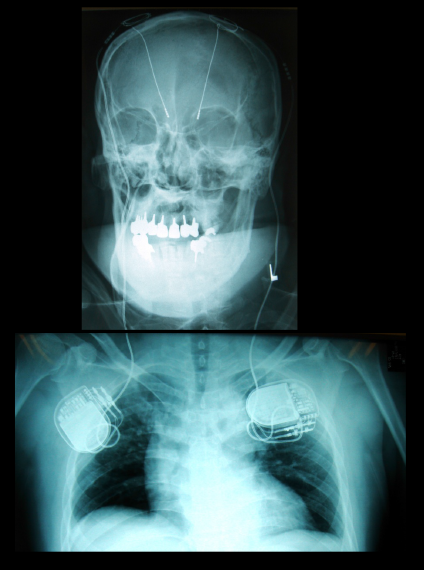

脳深部刺激療法(DBS)

img

1: 著者提供